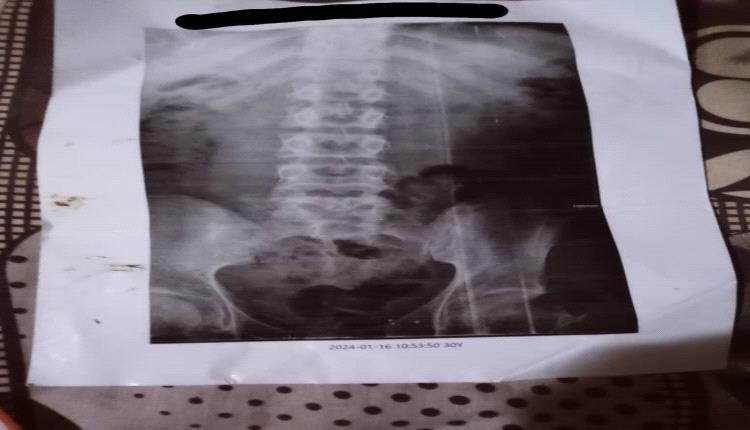

طفلة مصابة بضمور في المخ ونوبات صرع تناشد أهل الخير مساعدتها

طفلة مريضة عمرها ثلاث سنوات تعاني من ضمور في المخ وتجيها نوبات صرع وظهرها مقوس وما تسمع ولا ترى وتبكي على مدار الساعة ما تسكت الا لما تنام وما تنام إلا بأدوية ..